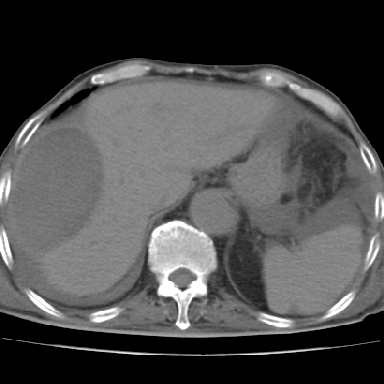

以下是引用qian在2006-12-4 19:11:00的发言:[br]胸腔和腹腔内均见有液性影,肝上极包膜下有一较大椭圆形低密度影,密度均匀,边缘清晰,结合病史考虑术后肝脓肿并胸腹腔积液。

以下是引用dyqct在2006-12-4 19:54:00的发言:[br]考虑:1、肝包膜下脓肿;[br] 2、少量腹水;[br] 3、右侧少量胸膜腔积液。